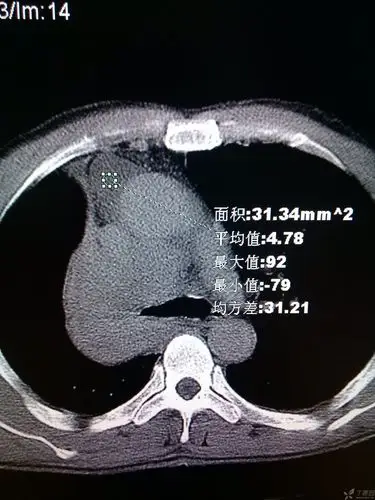

胸部x射线 ct增强片 帮帮忙看一下 是肺癌吗?